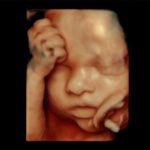

The pregnancy process, which is described as an extremely exciting expectation for parents, is also a period that requires close monitoring of maternal and infant health. One of the most important instruments that assist obstetricians in the follow-up process is imaging systems. During the examination, which usually starts from the 6th week of pregnancy, ultrasound imaging continues throughout the entire pregnancy period and sheds light on the experts about the development of the baby and the detection of extraordinary developments. Unlike the applications performed with 4D ultrasound systems between the 19th and 23rd weeks of pregnancy, thanks to Voluson E8, which provides much more detailed imaging thanks to its superior technology, possible anomalies in the baby can be detected more clearly or the health of the baby is ensured.

Talking about the advantages of Voluson E8, Prof. Dr. Müfit C. Yenen said, “The structure of the vessels has become easily visible and easier to diagnose thanks to the fast and easy imaging opportunity provided by E8 technology even in the thinnest and smallest vessel structures. Even the blood flow in the vessels has become visible. The shapes in the anatomical structure of the baby, whose development process continues in the womb, can be easily displayed thanks to the advanced volume contrast feature of the device. Critical measurements such as height, weight, head circumference and nuchal thickness, which are accepted as important indicators of baby's health, are made automatically by the device. Thus, the possibility of error in manual measurements has now been eliminated. Thanks to the technological superiority of the system, which also makes it possible to display the internal structures of the baby, extraordinary anatomical realism is provided in the images obtained.”